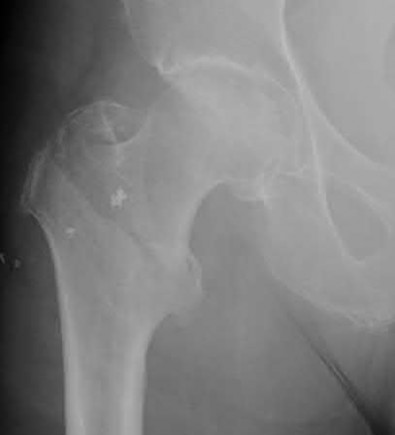

A 12-year-old obese boy presents with vague left thigh and knee pain. He is diagnosed with a Slipped Capital Femoral Epiphysis (SCFE) as seen in similar clinical scenarios.

During percutaneous in-situ fixation, unrecognized penetration of the guide wire into the hip joint occurs. What is the most likely specific complication resulting from this technical error?

Chondrolysis is a severe complication of SCFE characterized by rapid destruction of the articular cartilage. While it can occur idiopathically, its most established iatrogenic cause is unrecognized intra-articular hardware penetration. The 'approach-withdraw' fluoroscopic technique is required during pinning to assure pins are entirely intraosseous. Avascular necrosis (AVN) is usually due to damage to the epiphyseal blood supply (retinacular vessels) secondary to the initial displacement, forceful closed reduction, or posterosuperior pin placement.